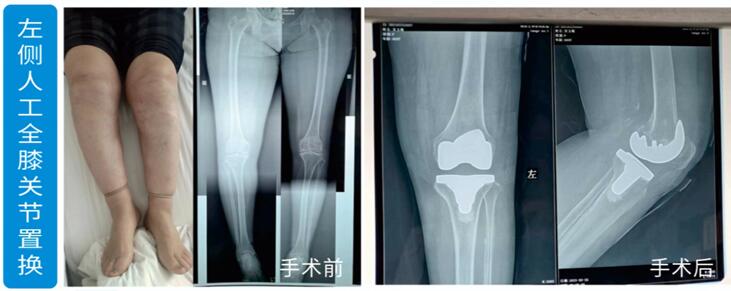

南阳文和骨科--左侧人工全膝关节置换

003.jpg